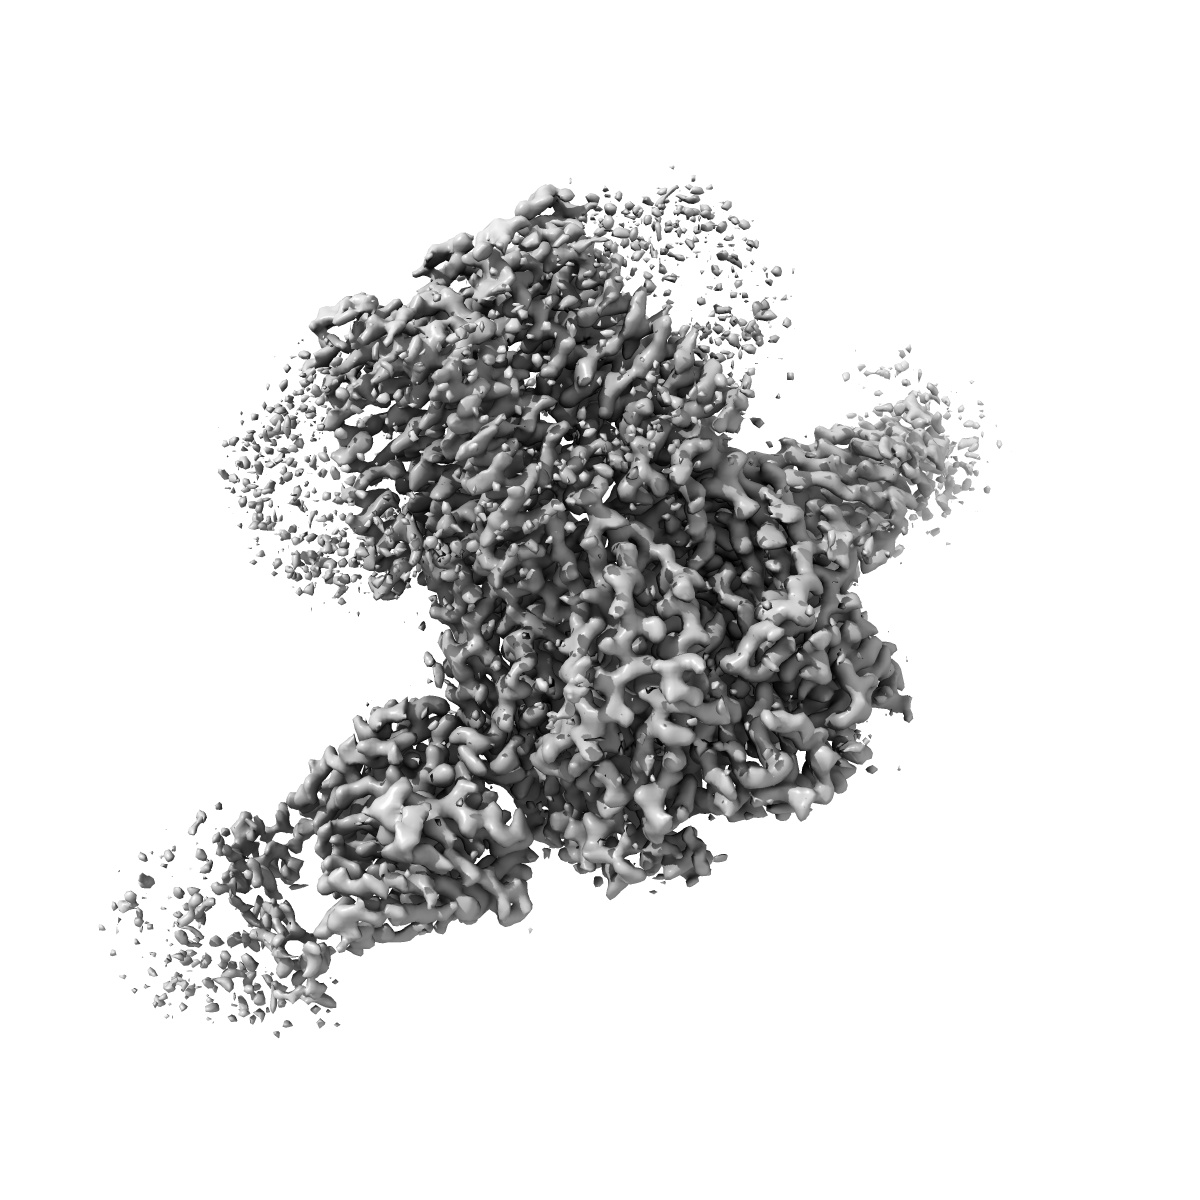

Human GABAA receptor alpha1-beta2-gamma2 subtype in complex with GABA plus picrotoxin

Sample: Human GABA-A receptor alpha1-beta2-gamma2 subtype in complex with GABA and picrotoxin

Single-particle

2.86 Å